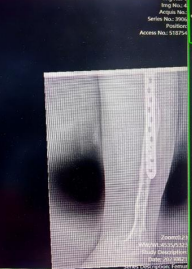

患者左股骨与胫骨骨折术后X光检查结果

说起李先生的病情,还要追溯到九年前的一场意外。在那场意外中,李先生左股骨与胫骨严重骨折,虽然在当地医院接受了手术治疗,但术后李先生小腿逐渐短缩畸形。这一变化不仅限制了他的日常活动,更是让他的生活笼罩在一层无形的阴影之中,极大地损害了心理健康。